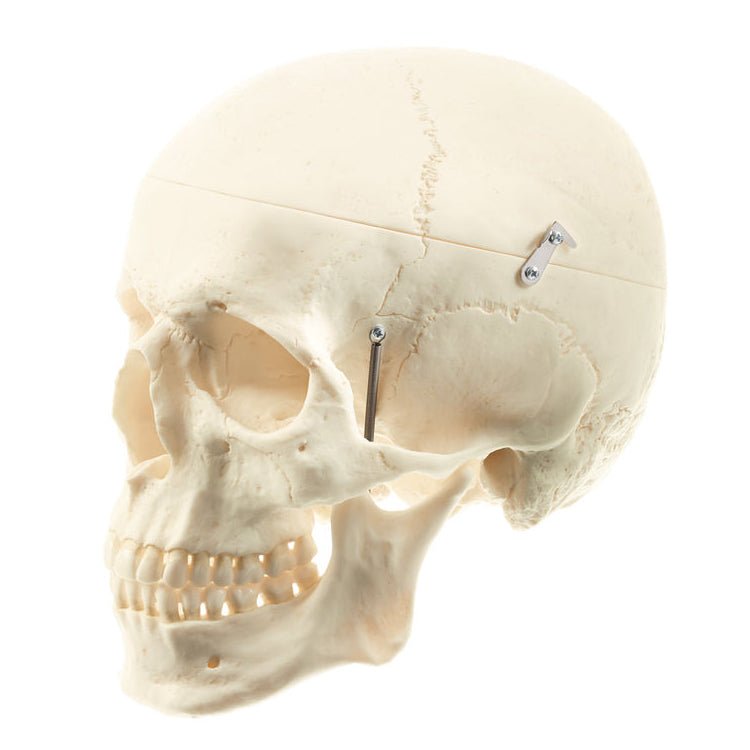

下記に商品説明や配送料・配送方法・注意事項等の説明がございます。Surgical Approaches to the Facial Skeleton | 9780781754996。W側頭骨 削開済 3 C12-3の医療模型 | 3DモデルのKEZLEX。

【インボイス制度対応済み】当社では2023年10月からインボイス制度に対応した適格請求書発行事業者番号(通称:T番号・登録番号)を印字した納品書(明細書)を商品に同梱してお送りしております。こちらをご利用いただくことで、税務申告時や確定申告時に消費税額控除を受けることが可能になります。Search - Endonasal skull base surgery | KARL STORZ Endoskope。CAS: Asymmetry correction for Laterognathia。どちらのサイトからもご購入可能です。